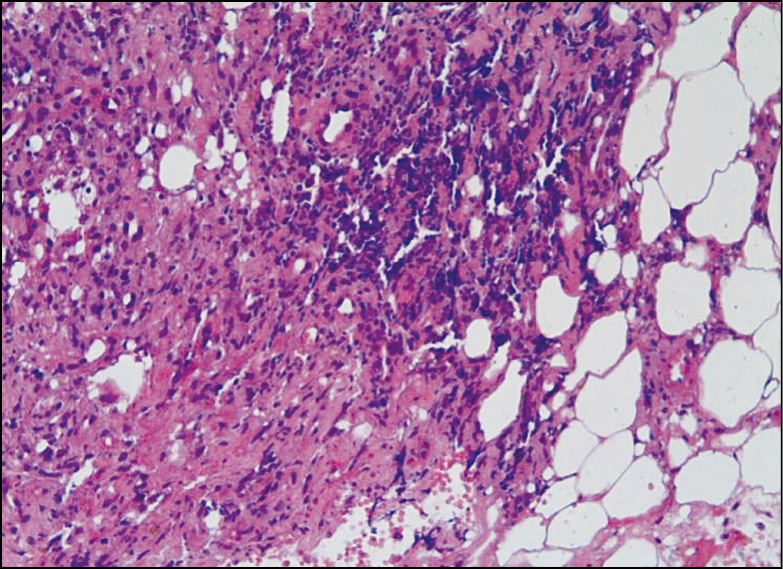

Рис. 2

Патогистология. В препаратах кожи обильная нейтрофильная инфильтрация дермы и гиподермы с формированием подэпителиальных абсцессов, явления лейкоцитокластического васкулита.

Патогистология. Характерными для ГП гистологическими признаками являются обильный нейтрофильный инфильтрат в дерме с формированием микроабсцессов, лейкоцитокластический васкулит с повреждением сосудистой стенки, экстравазация фибрина и эритроцитов [6].